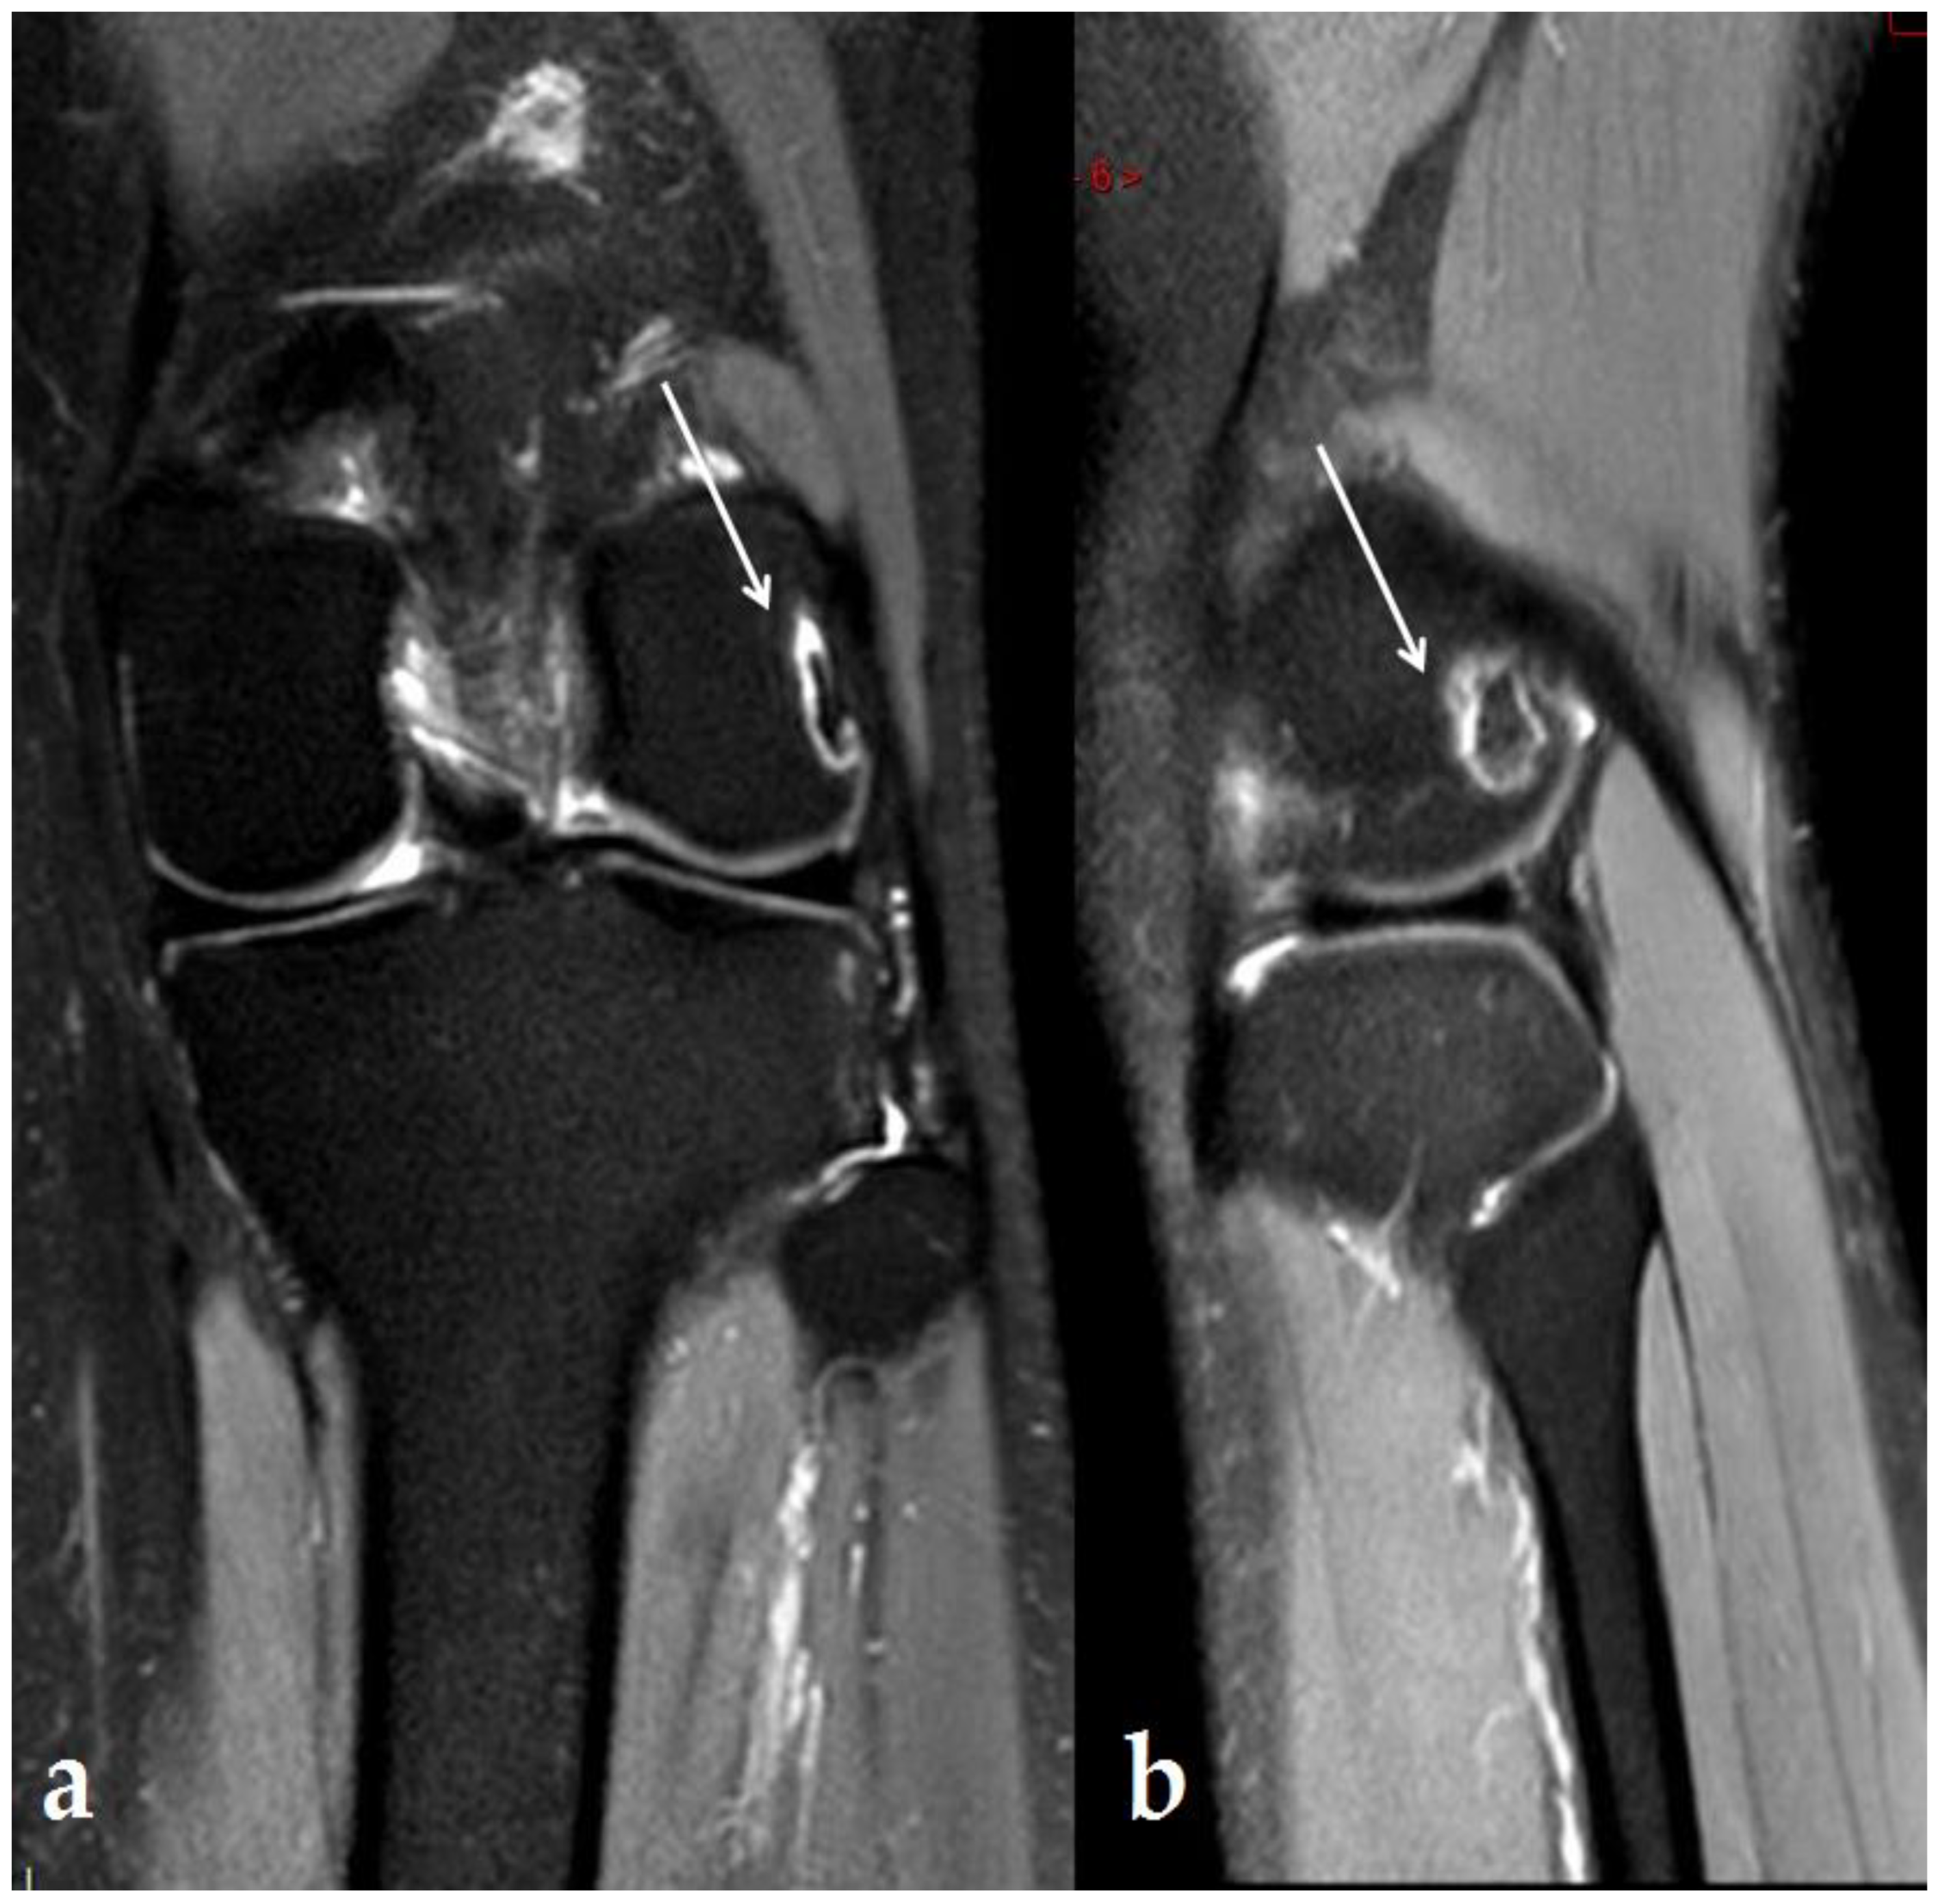

2. Case Report

3.1. Knee Lesions Encountered

3.1.2. Osteonecrosis Lesions of the Knee

- “Osteonecrosis-like” lesions reported in the literature